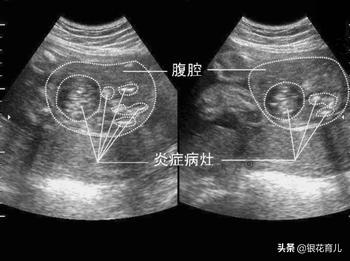

胎粪性腹膜炎是胚胎期由于某些原因造成肠道穿孔,胎粪进入腹腔,引起无菌性、异物性和化学性炎症的结果。

胎儿因肠梗阻阻碍胎儿吞咽羊水的运行,孕妇多伴有羊水过多,X线检查显示胎儿腹腔内有钙化斑块,一般就能确诊。